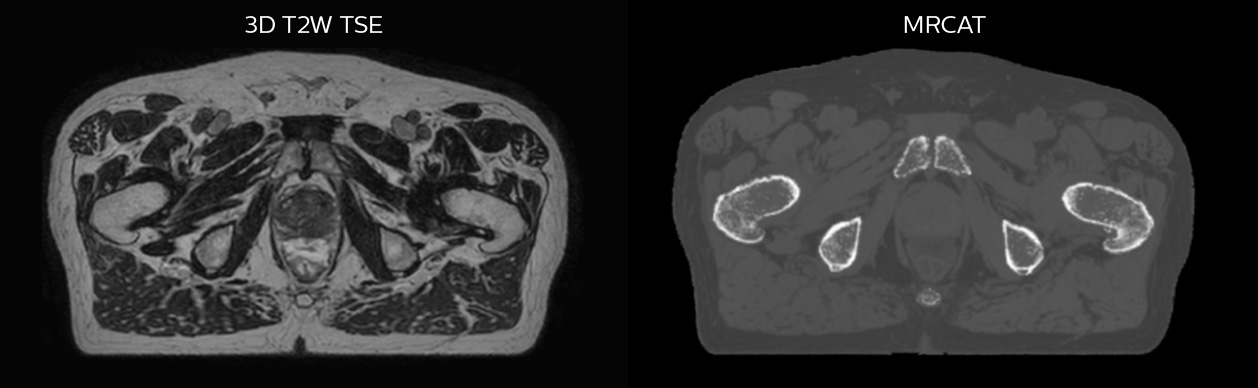

Simulation imaging

Tranversal 3D T2W TSE with Compressed SENSE, acquired on Ingenia MR-RT 1.5T (left).

On-console generated MRCAT (right).